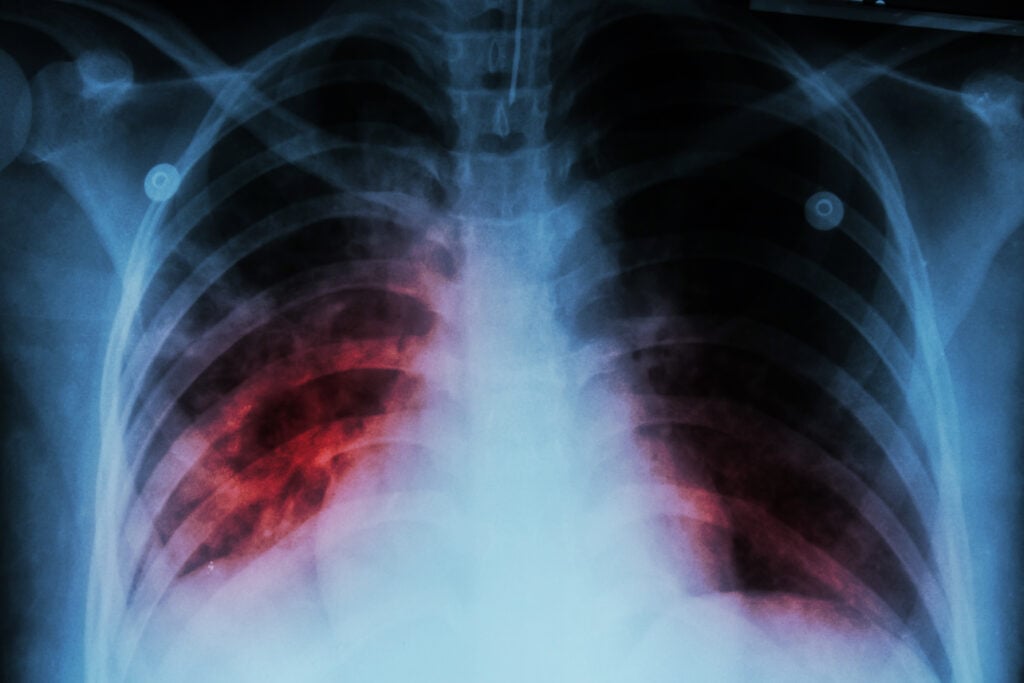

Ho ra máu là một trong những dấu hiệu cảnh báo căn bệnh ác tính nguy hiểm đến tính mạng – ung thư phổi. Ho thường kéo dài dai dẳng, ban đầu ho kèm theo máu đỏ tươi, có thể có bọt hoặc chất nhầy. Sau đó, máu dần chuyển sang màu đen.

Các triệu chứng khác của ung thư phổi bao gồm khó thở, đau ngực, khàn giọng, nổi hạch ở cổ, chán ăn và sụt cân. Bác sĩ có thể chẩn đoán ung thư phổi bằng một số phương pháp như: Chụp CT, Chụp X-quang, Xét nghiệm đàm,…